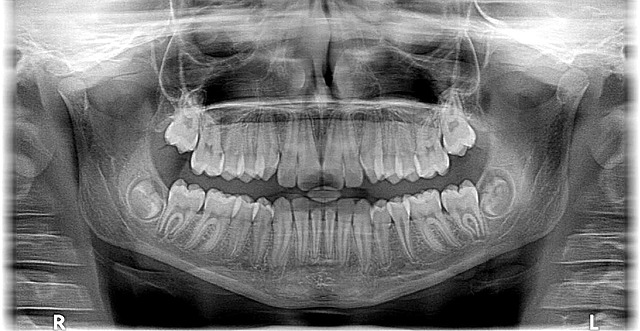

사랑니는 똑바로 나기도 하지만, 잇몸 속에 묻혀 있거나 옆으로 누워있는 경우도 많습니다. 치과에서 엑스레이 촬영을 통해 다음과 같은 상태를 확인해야 합니다.

- 완전 맹출: 똑바로 나와서 씹는 기능을 하지만 충치 위험이 있는 경우

- 부분 매복: 일부만 나와 있어 음식물이 끼기 쉽고 염증 위험이 높은 경우

- 완전 매복: 잇몸 아래 깊이 묻혀 있고 주변 치아를 밀거나 신경과 가까운 경우

아래턱 사랑니가 신경과 가까운 경우 드물지만 감각 이상이 발생할 수 있습니다. 이러한 위험을 줄이기 위해 반드시 엑스레이나 CT 촬영을 통해 신경과의 거리를 확인하세요.

- 엑스레이 촬영을 통해 사랑니 상태를 정확히 확인하기